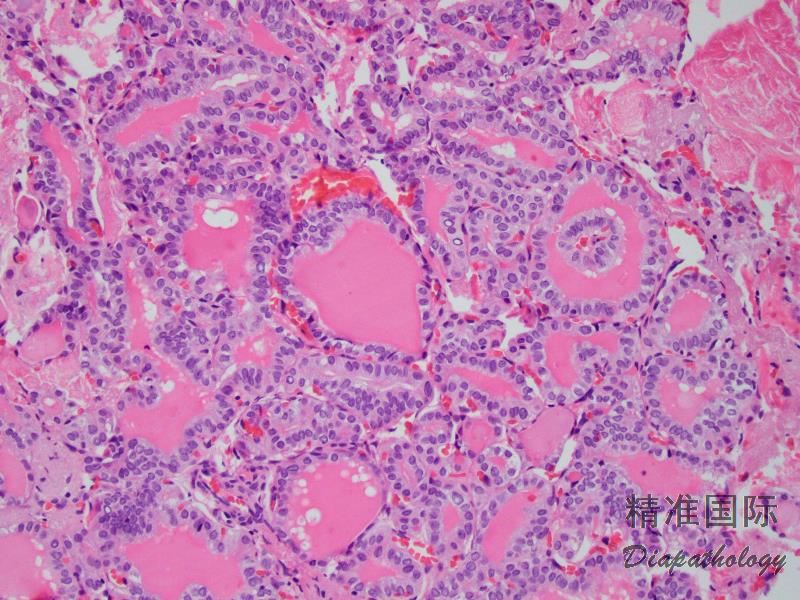

滤泡长而不规则,可以是微滤泡、正常滤泡或大滤泡;

无或很少乳头结构(乳头成分<1%);

可伴有实性、梁状、岛状生长方式,但一般不超过 30%;

细胞核和甲状腺乳头状癌核特征相似,核增大,重叠,卵圆形或短梭形,典型的核为清澈的或毛玻璃样,核形不规则,常 见核沟和核内假包涵体;

胶质深嗜伊红色伴周边吸收空泡;

部分病例滤泡腔内可见多核巨细胞。